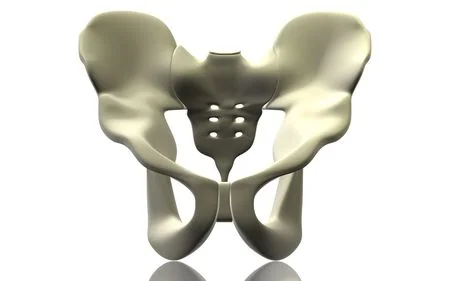

La cintura pélvica, también conocida como cingulum pelvicum o cintura pelviana, es la estructura ubicada en el extremo inferior de la columna vertebral y está formada por los huesos coxales. La función principal de la cintura pélvica es unir los miembros inferiores al tronco y proporcionar soporte y estabilidad para el cuerpo.

Los huesos coxales, también llamados huesos de la cadera, son un par de huesos grandes y resistentes que se unen en la parte anterior del cuerpo para formar la estructura de la pelvis ósea. Cada hueso coxal está compuesto por tres huesos fusionados: el ilion, el isquion y el pubis. Estos huesos se articulan entre sí en el acetábulo, una cavidad profunda en la que se inserta la cabeza del fémur (hueso del muslo) para formar la articulación de la cadera.

La cintura pélvica desempeña varios roles importantes en el cuerpo humano. En primer lugar, proporciona una base sólida y estable para el tronco y los órganos internos. Los huesos coxales son resistentes y capaces de soportar el peso del cuerpo y las cargas transmitidas durante el movimiento y la actividad física. Además, la cintura pélvica protege los órganos de la cavidad pélvica, como el útero, la vejiga y los órganos reproductivos.

Otra función clave de la cintura pélvica es la conexión de los miembros inferiores al tronco. Los huesos coxales se articulan con el fémur en las articulaciones de la cadera, lo que permite el movimiento de las piernas. Estas articulaciones son esenciales para la locomoción y proporcionan estabilidad y movilidad necesarias para caminar, correr, saltar y realizar otras actividades físicas.

Además de su función de soporte y conexión, la cintura pélvica también tiene un papel importante en el parto en las mujeres. Durante el embarazo, los huesos coxales se ensanchan y se flexibilizan para permitir el paso del bebé a través del canal del parto. Esta adaptabilidad de la cintura pélvica es esencial para facilitar el proceso de parto vaginal.